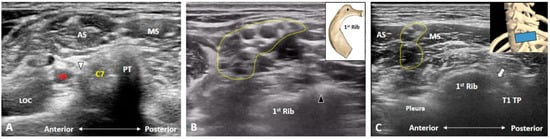

2. Anatomy

3. Imaging for Normal BP

3.1. Should We Start the Scanning Cranially?

3.2. Is the C7 Transverse Process Easily Recognized?

3.3. How Can We Locate the C8 and T1 Roots?

3.4. How Can We Better Visualize Cervical Anterior Rami during the Scanning Process?